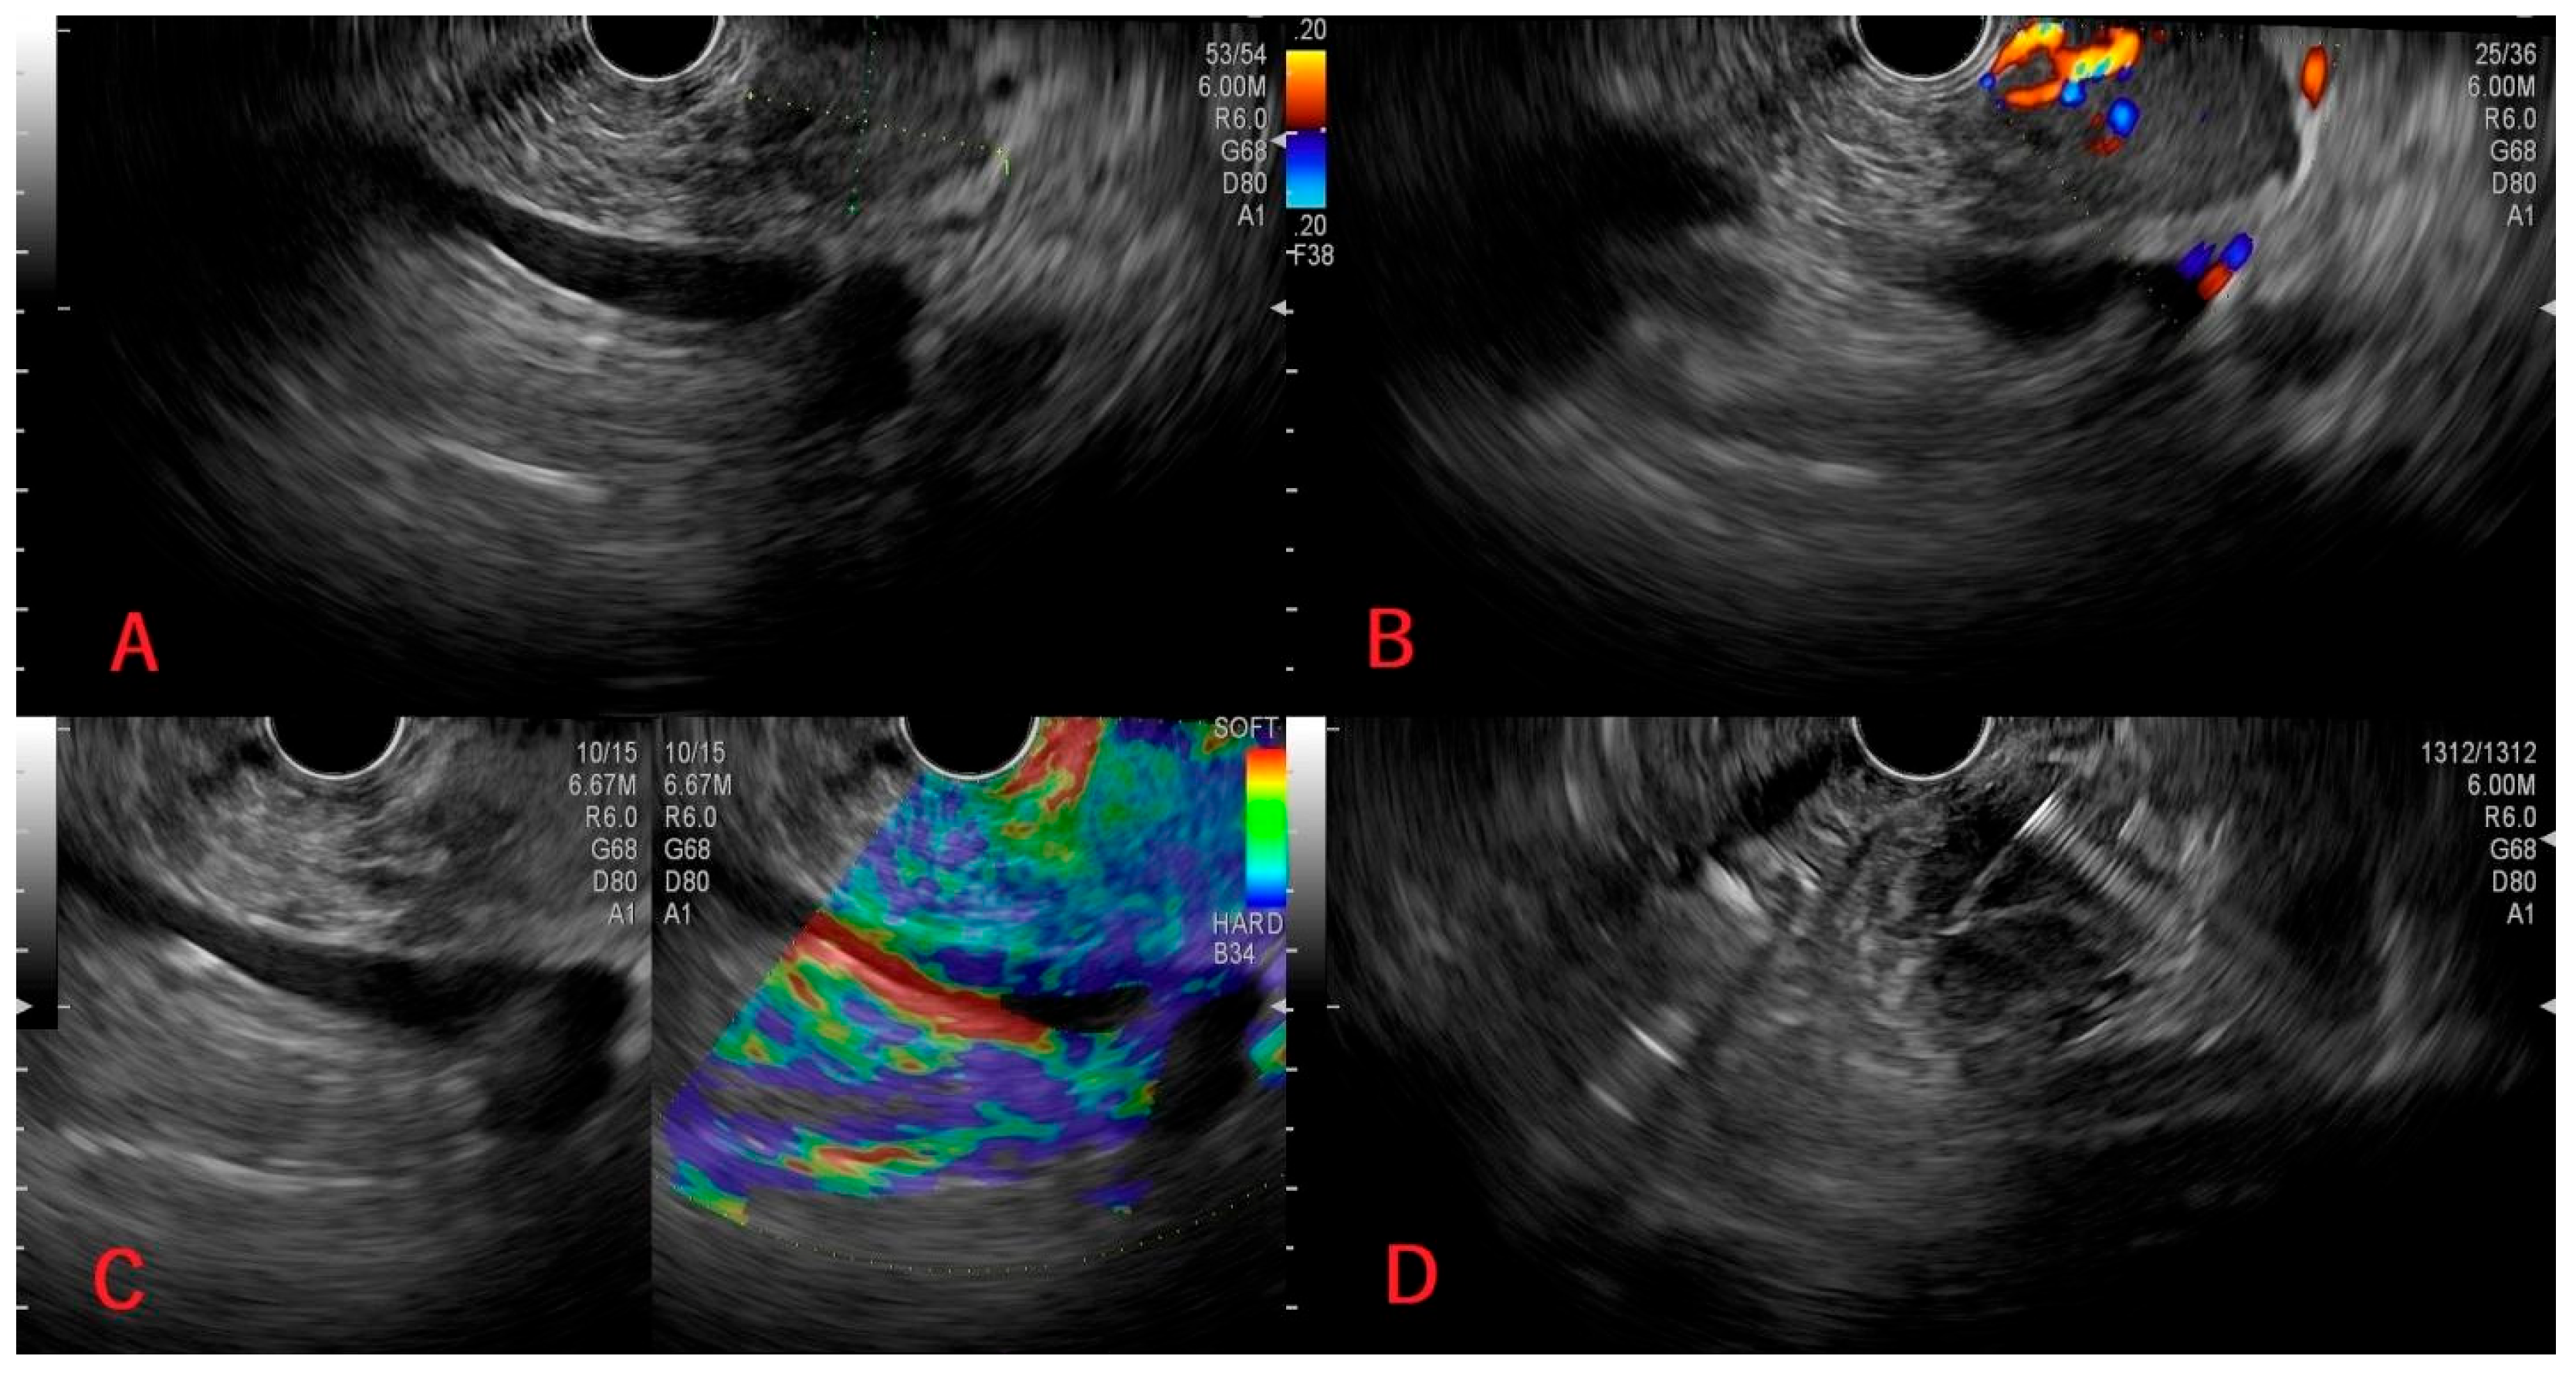

| 1 | 65/M | Incidental lesion on CT (admission for cholecystectomy); renal tumor diagnosed during the same presentation; cardiovascular comorbidities. | Cephalic, 22/16 mm. | Hypoechoic, well-demarcated, relatively homogeneous; accentuated intratumoral vascular flow; hard consistency. | Negative: chromogranin, synaptophysin, CK7, CK20. Positive: cytokeratin AE1/AE3, CD10, vimentin, PAX8 and CAIX. | No significant short-term complication. | CT→EUS with FNA→Single-stage nephrectomy + cephalic duodenopancreatectomy; oncologic treatment; favorable outcomes at 3-year follow-up. |